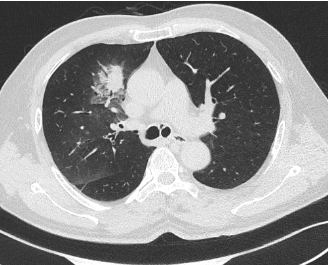

术后患者CT

术后患者咳嗽、咳痰症状显著缓解,目前正接受抗感染、抗炎、化痰及营养支持等个性化康复治疗。此例手术的成功标志着我院呼吸介入诊疗水平取得重要突破,为因身体条件无法耐受常规手术的肺癌患者提供了新的、有效的微创治疗选择,充分体现了医院在复杂肺部疾病综合诊疗领域的实力。